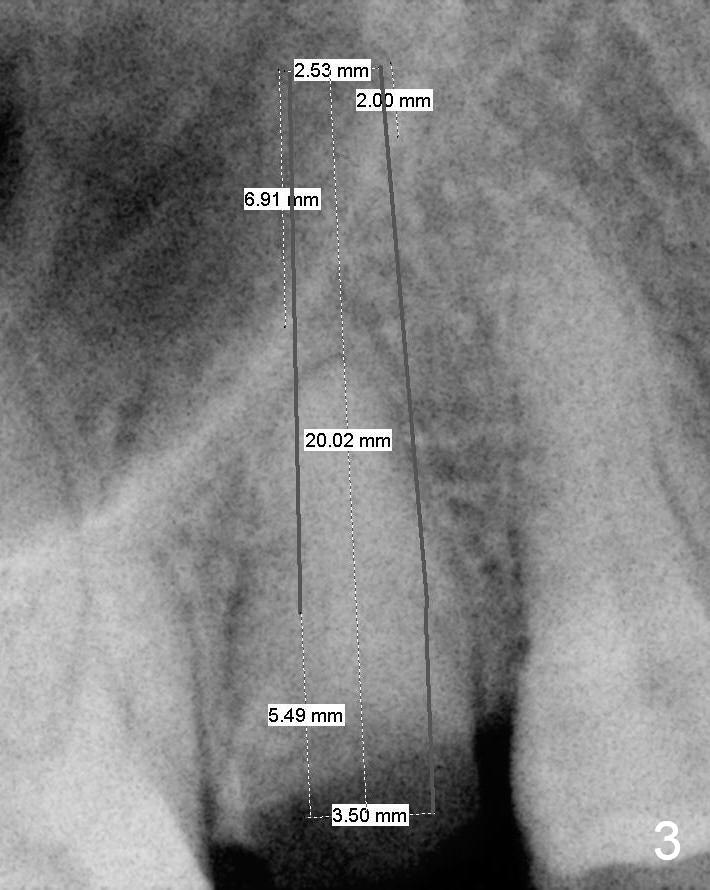

A 52-year-old woman (LP) has postponed extraction and implant for the tooth #4 for 10 years (Fig.1). The socket is oval in cross section, great site for D Implant. D2 (3.5x4.5 mm) short (16 mm, Fig.2) and long (20 mm, Fig.3) implants appear to be fit for the site (no antibiotic). However, placement of the latter involves bone expansion/tapping, which is incompatible with the fearful lady. Let us be gentle (Fig.4).